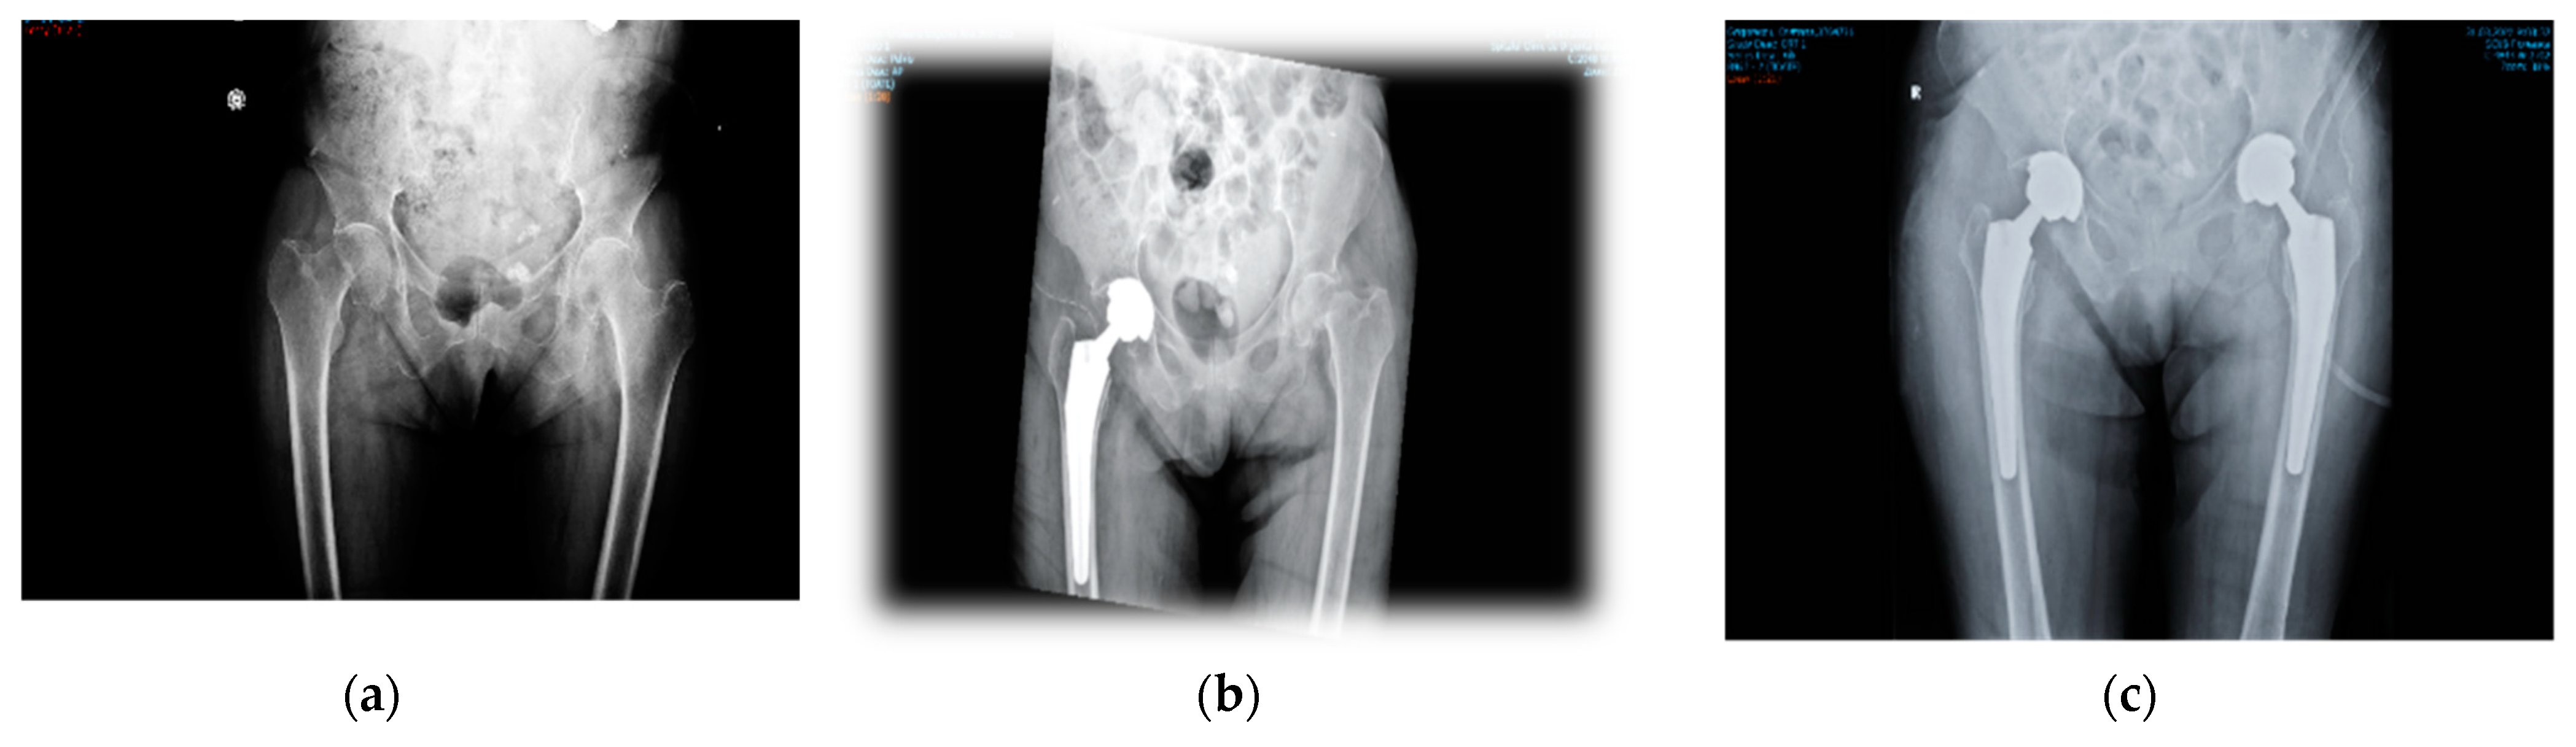

- surgery and appropriate manipulation and fixation of the bones, using the most suitable devices (screws, cables, cement/non-cement prostheses, etc.).